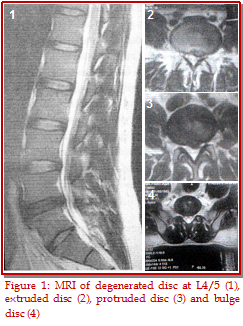

There are contradictory reports on the findings of magnetic resonance image (MRI) in lumbar intervertebral disc prolapse. A study was conducted on 54 patients using 3 of 4 clinical criteria (low back pain with radiation down to the lower limbs, radicular pain along specific dermatomes, positive straight leg raising test, presence of neurological symptoms and signs e.g. motor or sensory deficit and MRI of lumbosacral spine of the respondent). Evaluation of MRI of lumbosacral spine was done based on extent of disc prolapse, disc degeneration, nerve root compression neural foramen compromise. The logistic regression analysis between the findings of MRI and the clinical features show that there was a significant association in the neural foramen or lateral recess (Odd's ratio 7.106, p<0.05), the root compression (p<0.01) as well as the disc extrusion (p<0.05). There was no statistical association between clinical levels and other MRI findings like disc protrusion and disc bulge (p value 0.21 and 0.14, respectively). The strength of agreement between clinical and MRI diagnosis level of disc prolapse was calculated using kappa statistics (k-value). The test revealed a very good agreement for L3/4 (k-value = 0.812) and good agreement for L4/5 and L5/SI level (k-value 0.75 and 0.75 respectively) between these two procedures, suggesting that level of disc prolapse could be correctly diagnosed without MRI findings. In conclusion, clinically diagnosed levels associate well with MRI levels, but all MRI abnormalities do not have any clinical significance.